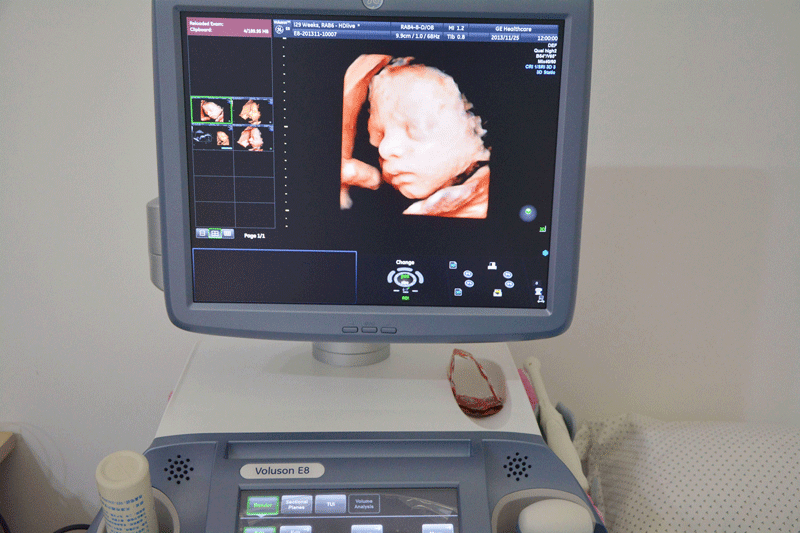

三维彩超,即彩色多普勒超声检查的一种,检查图像呈土黄色,通过多普勒超声仪器发出超声波,对体内各项器官进行成像。三维即其图像是立体的,可以更直观的看到器官的形态,及时发现病变并进行治疗。三维彩超常用于产检,用来判断胎儿的生长发育的情况或是否出现畸形等。

四维和三维彩超有区别

3、二者的成像方式有区别

三维和四维并不是彩色图片,只是和黑白色有差异,二者呈现的都是土黄色的画面。但三维的成像是静态的,是一张图片,而四维彩超则是动态的,像一张动图一样,并且有的医院会允许刻成光盘带回家收藏起来。